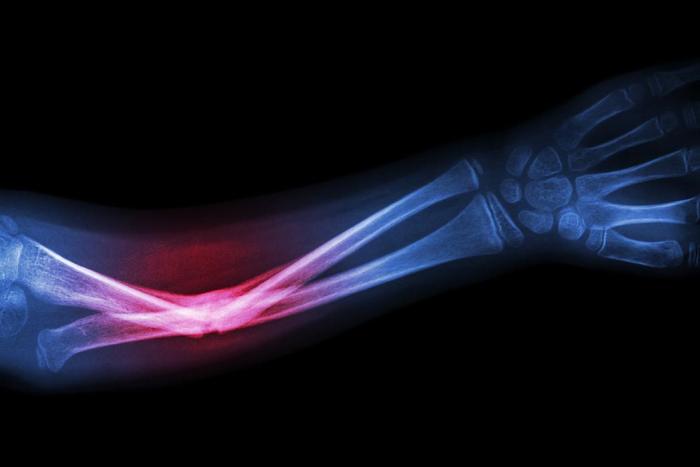

El diagnóstico por imagen cada vez tiene más relevancia en la medicina. Las técnicas de radiodiagnóstico para patologías del sistema músculoesquelético han ido evolucionado rápidamente en los últimos años debido al desarrollo de las nuevas tecnologías y la bioingeniería. El conocimiento de estos avances, de las técnicas y su implementación en el proceso médico, hacen imprescindible una constante actualización por parte del médico especialista.

Actualizar al médico especialista en los últimos procedimientos y las técnicas que se realizan en el proceso del diagnóstico de las patologías en el sistema músculoesquelético incorporando estos últimos avances en la disciplina para aumentar la calidad de su práctica médica diaria y mejorar el pronóstico del paciente

El principal objetivo está orientado a permitir la incorporación de los avances que se van produciendo en el abordaje diagnóstico de las patologías del sistema músculoesquelético, procurando que el especialista pueda actualizar sus conocimientos de un modo práctico, con la última tecnología educativa y adaptando el proceso educativo a sus necesidades reales.